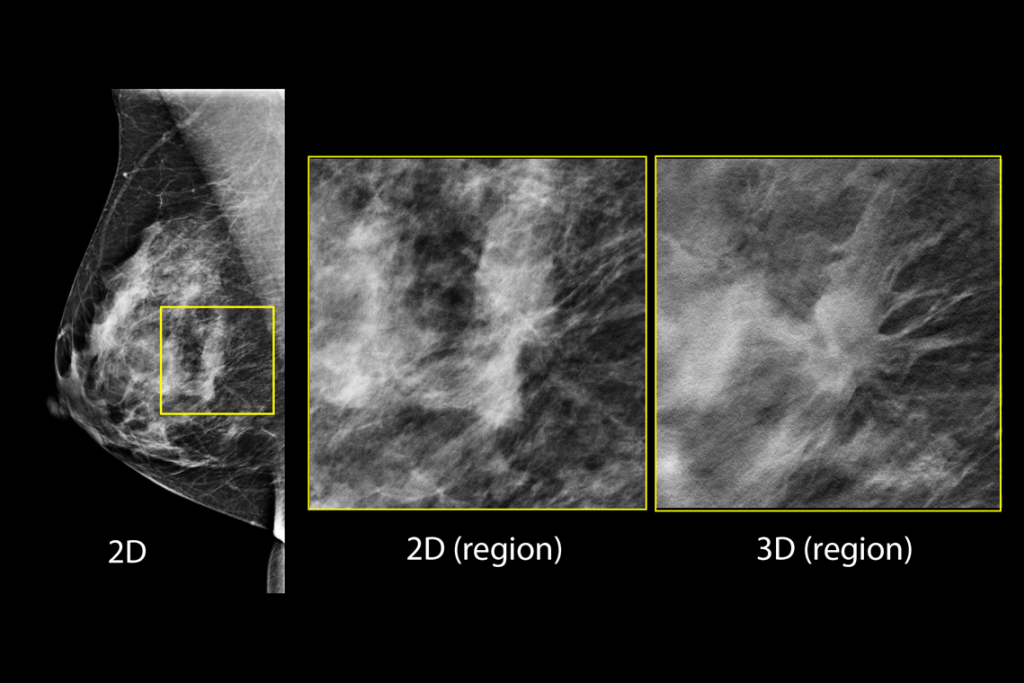

乳房検査の臨床画像

脂肪性乳房の乳房検査の臨床画像